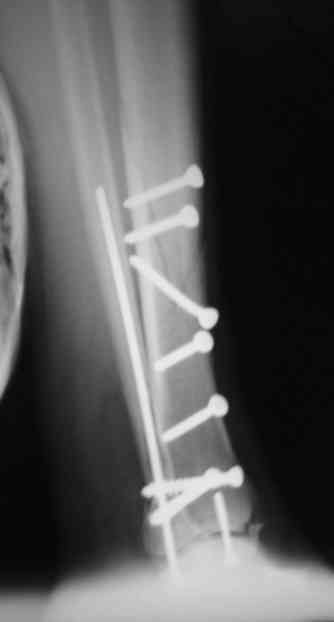

Re: Сложный внутрисуставной перелом голени

Рентгенограммы